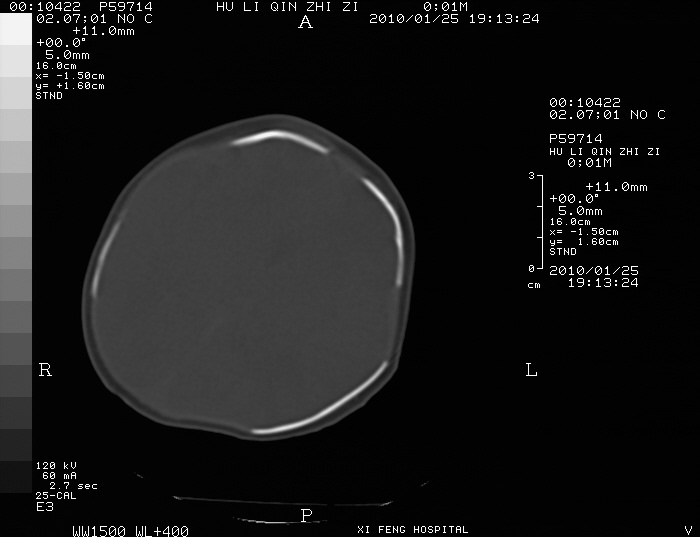

男  新生儿,曾做b超股骨长5.5厘米,疑畸形,家族中有多个身才矮小.曾孕两次,一次流产,一次宫内死亡

四肢干骺端呈喇叭口型缺损,颅骨缝增宽,支持软骨发育不全。